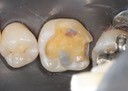

Joe Cha #3 amalgam removal